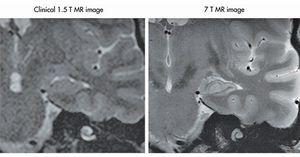

Comparison of a medium and an ultra-high field MRI system. 7.0 Tesla MRI system provides high quality imaging of the hippocampus.